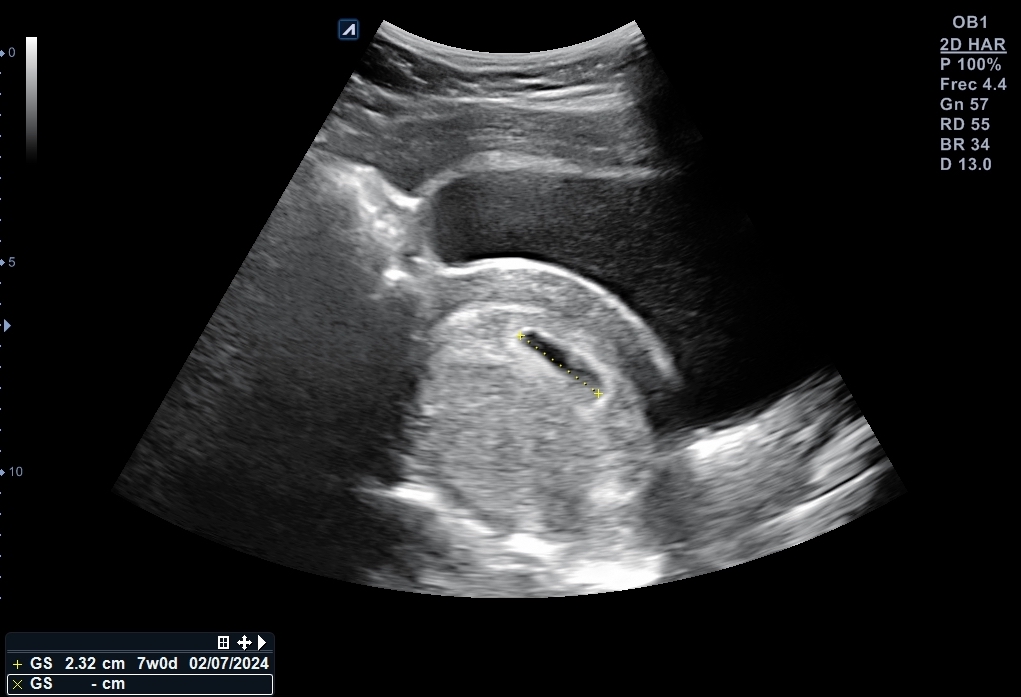

Se explora pelvis con sonda cónvex: vejiga distendida de paredes lisas y homogéneas. Útero en anteversión con endometrio decidualizado y saco embrionario en su interior, bien posicionado con una estimación de 6 + 2 semanas de gestación. Se localiza cuerpo lúteo en anejo izquierdo que, además está aumentado de tamaño.

Nueva ecografía: saco embrionario con embrión con latido fetal a 135 lpm y se data de 6 + 4 semanas. Se cita para analítica de primer trimestre, así como con Obstetricia.